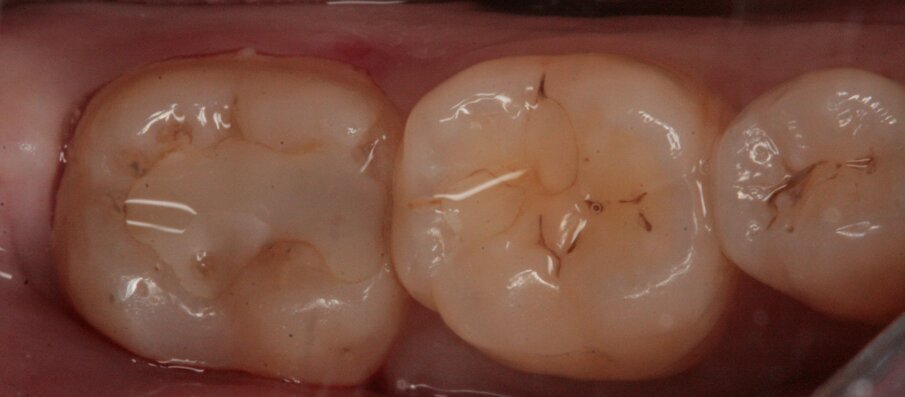

Gli elementi da trattare, 36 e 37, all’esame obiettivo presentano leggeri solchi intaccati dal processo carioso (Figg. 19, 20); clinicamente la dentina viene interessata perciò si procede al restauro mediante due masse, una dentinale e una smaltea (Figg. 21, 22).

Fig. 19_Restauro presente nell’elemento 37 e solchi interessati dal processo carioso dell’elemento 36.